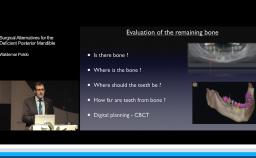

This lecture reviews in detail the various defects encountered in clinical practice that may need regenerative procedures for hard and soft tissue augmentation. The presentation is supported with excellent visual aids that illustrate how these defects can be reconstructed for prosthodontically driven implant placement. It also addresses how to prevent complications in regenerative and reconstruction procedures as well as the predominant treatment options to manage these complications. Clinical outcomes are supported by reference to several studies and clinical recommendations from the 4th ITI Consensus Conference.

- describe the various bone defects encountered in clinical practice to be considered before implant placement